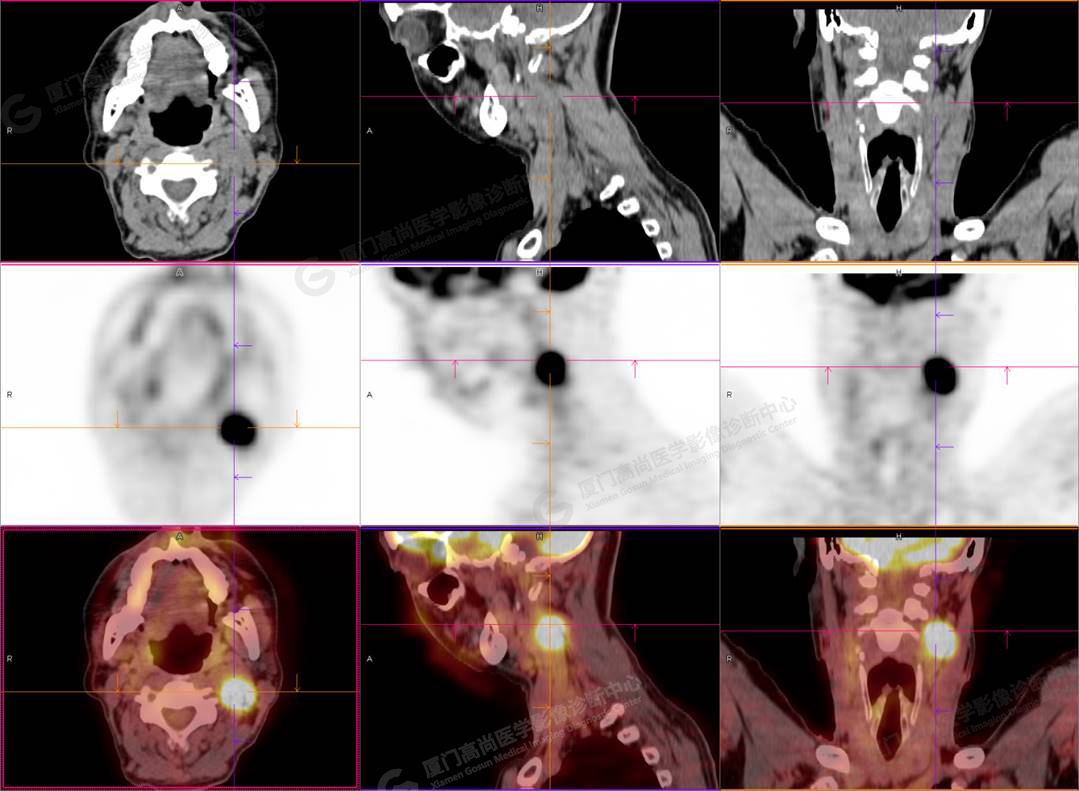

PET/CT影像圖

圖1

PET/CT所見:左側頸部(II區(qū))見腫大淋巴結,大小約2.5cm×2.3cm,其內密度不均,邊界尚清,放射性攝取異常增高,早期SUVmax 11.5,延時SUVmax 14.5。

影像診斷: 左側頸部(II區(qū))腫大淋巴結,代謝異常增高,考慮腫瘤性病變可能性大(淋巴瘤?轉移瘤?),建議病理學檢查明確。